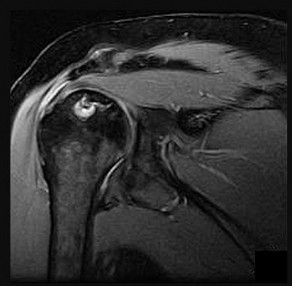

A 22-year-old collegiate baseball pitcher presents with vague posterior shoulder pain and a 25-degree loss of internal rotation (GIRD) compared to the contralateral side.

An MRI reveals a type II SLAP tear. The 'peel-back' mechanism is widely considered the primary etiology of this lesion in overhead athletes. During which phase of the throwing motion does the 'peel-back' mechanism occur?

Explanation

The 'peel-back' mechanism occurs during the late cocking phase of throwing, where the shoulder is in maximal abduction and external rotation. In this position, the biceps vector shifts posteriorly, creating a torsional force at the base of the biceps anchor that 'peels back' the superior labrum from the glenoid rim.